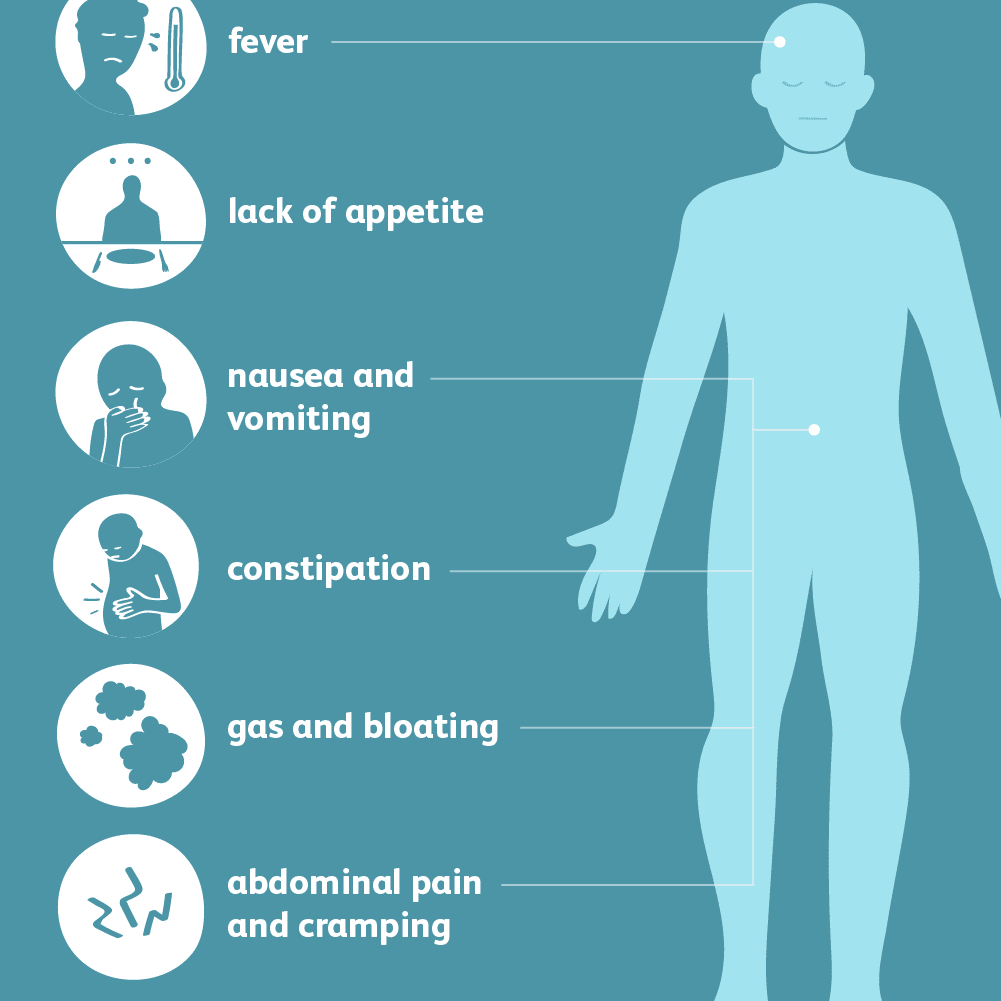

Gases In Stomach Infographics Health Concept. Symptoms And Treat …

Stomach Gas: Causes, Picture, Symptoms And Treatment

Stomach Gas: Causes, Picture, Symptoms And Treatment

What Does Gas Pain Feel Like? Stomach Upset vs. Gas Pain

Gas and bloating is an inflammation of the lining of the stomach.The …